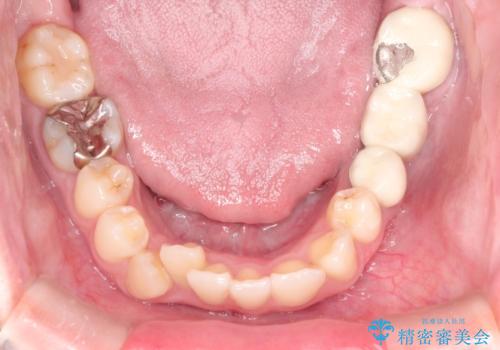

- 八重歯と前歯のガタガタを主訴に来院されました。

左下の奥歯がすでに1本抜歯されており、ブリッジを装着されていました。

ブリッジを除去して、左下以外の上顎両側と右下の歯を合計3本抜歯して矯正する計画としました。